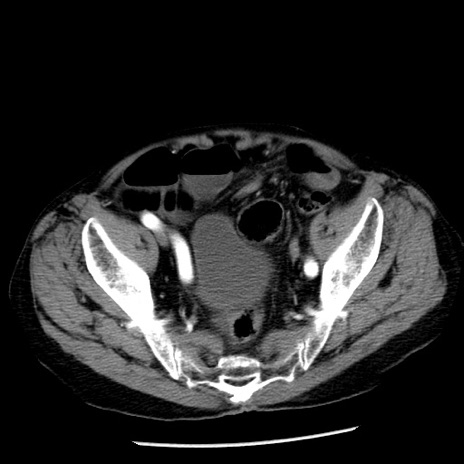

症例26(横断像)

【症例】80歳代男性

【主訴】嘔吐

【現病歴】昨晩2回嘔吐あり、今朝になっても嘔吐あり。来院。

【既往歴】胃潰瘍

【身体所見】意識清明、BT 37.6℃、BP 166/95mmHg、HR 100bpm、SpO2 97%、腹部:平坦・軟、腸蠕動音聴取良好、圧痛なし。

【データ】WBC 21900、CRP 1.46